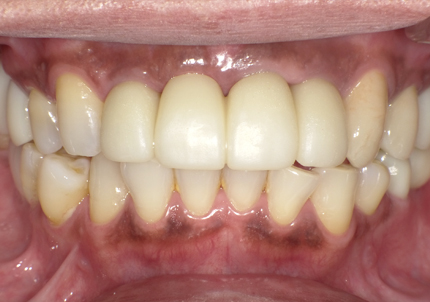

1.初診時口腔内写真(2018年10月)

1.初診時口腔内写真(2014年6月)